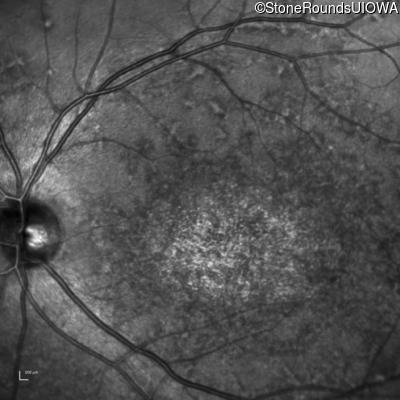

Infrared Fundus Photograph - Left - 20/200

Exemplar